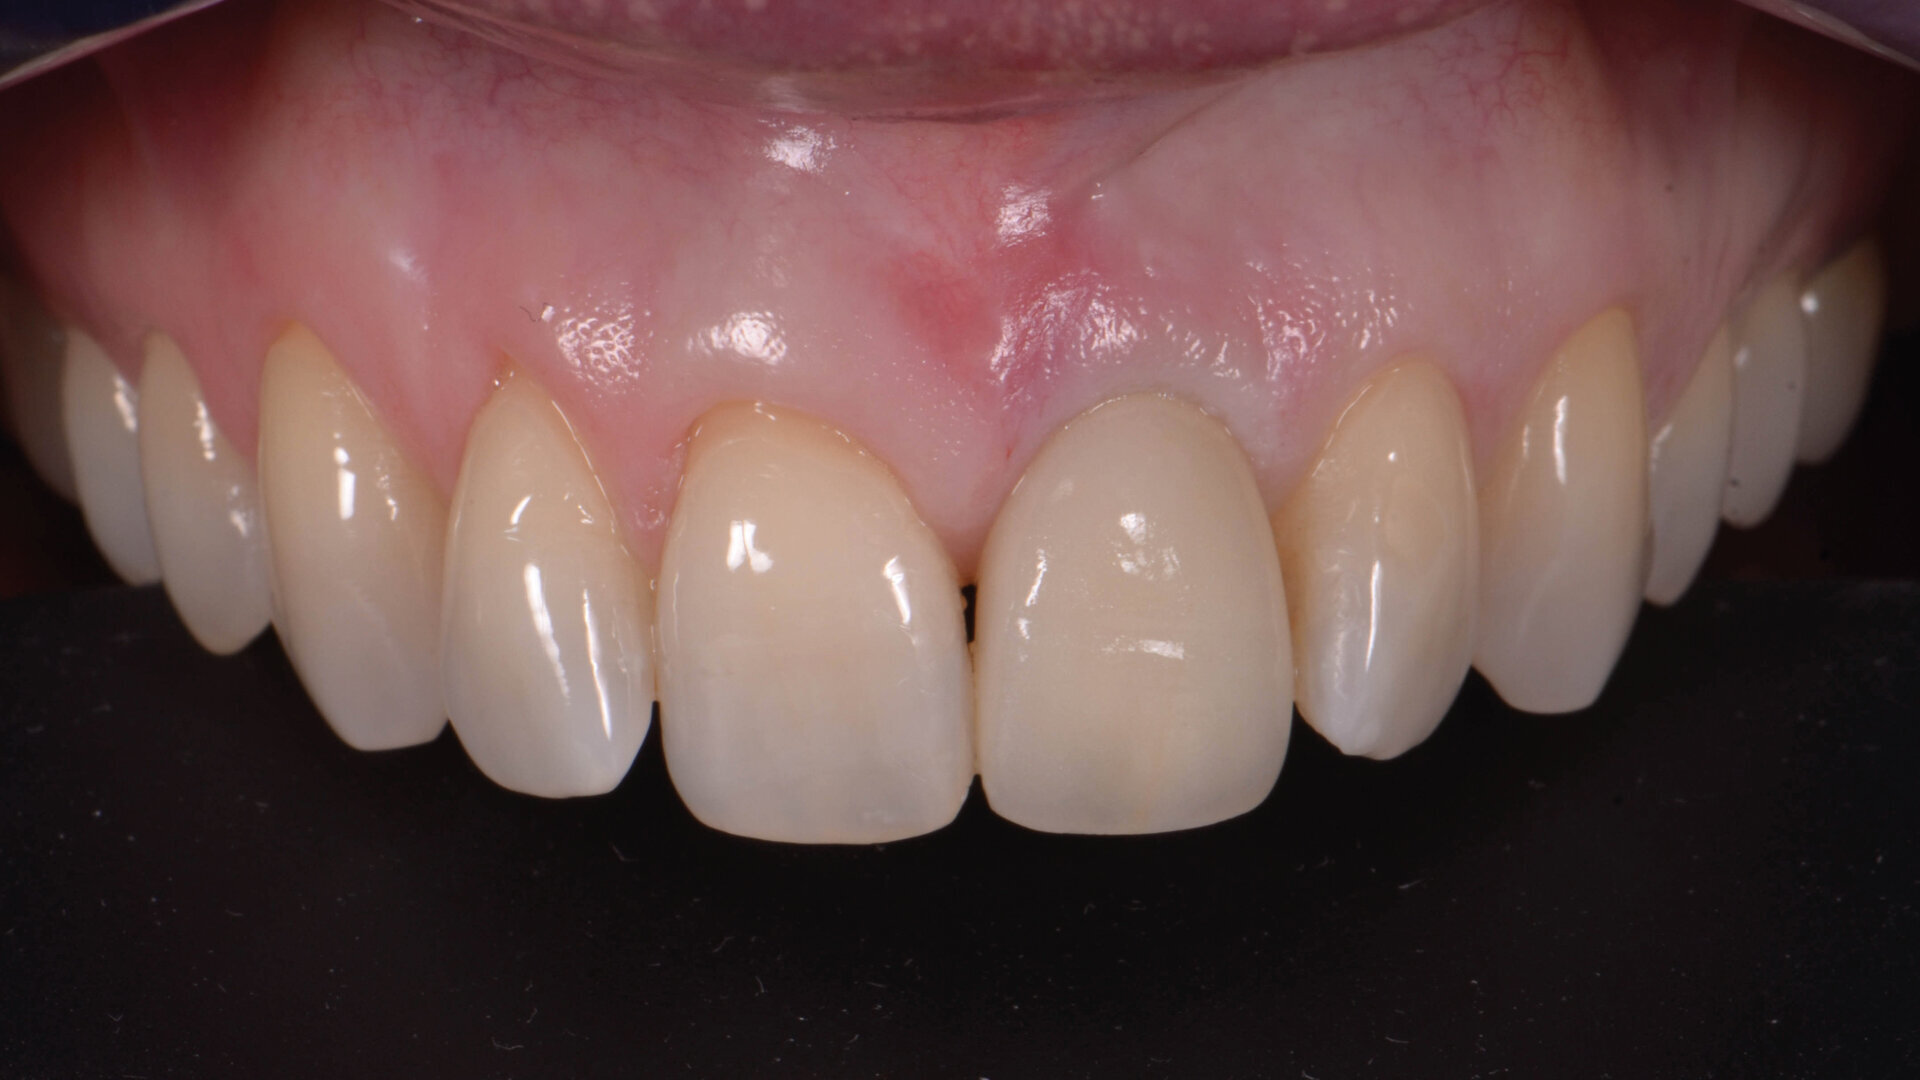

Après un délai de quatre mois postopératoires, la cicatrisation du site est obtenue (Fig. 9) : les tissus mous sont positionnés de manière optimale et les papilles préservées. Le volume osseux est également bien conservé.

Aucune concavité vestibulaire n’est présente et le contour de crête est correct. À ce stade, l’objectif principal est atteint : la cicatrisation post-extractionnelle est atteinte. La priorité passe des lors a la préservation de l’architecture des tissus lors de la phase implantaire. À cet effet, un protocole combinant l’élévation d’un lambeau de petite étendue et une chirurgie guidée avec forage pilote est alors exécuté (Fig . 10).

Un implant (Aadva Regular, GC Tech), avec une connexion conique interne associée au concept du platform switching, est mis en place (Figs. 11–12). La dent provisoire est ensuite collée à nouveau aux dents adjacentes

(Fig. 13a). Au bout de quatre mois, l’ostéointégration de l’implant est obtenue et cette fois encore, les tissus mous sont bien intégrés (Fig. 13b). La phase prothétique peut alors débuter.

Fig. 9 a: Après une période de cicatrisation de quatre mois

Fig. 9 b: Après une période de cicatrisation de quatre mois.

Fig. 9 c: Après une période de cicatrisation de quatre mois.